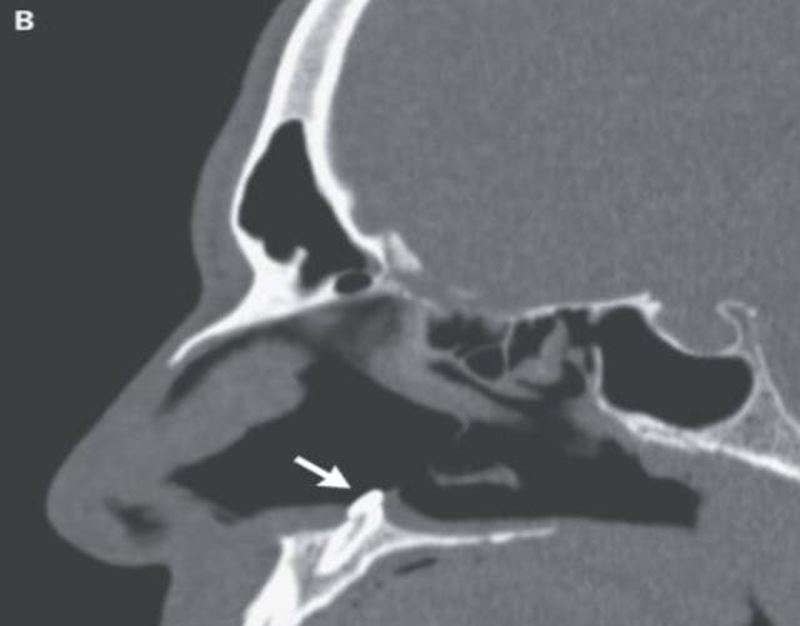

But after a doctor used a rhinoscope to make sure, which is a tool for inspecting the interior of the nose, they discovered that the man had a hard object lodged in his nostril.

A CT scan revealed the startling diagnosis: a tooth growing inside the nasal cavity.

Medically, the man had an “inverted ectopic tooth” which developed in his nose. Ectopic teeth are when teeth grow in the wrong places which are extremely rare.